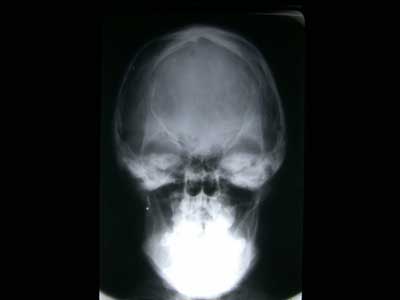

– Escafocefalia: Es el cierre de la sutura sagital. Es la deformidad más frecuente (50%). El cráneo adopta la forma de la quilla de un barco (de ahí su nombre), con un aumento del diámetro fronto-occipital (también se denomina dolicocefalia) y una disminución del diámetro biparietal (Fig.6)

Ya cada vez es más raro que diagnostiquemos una craneoestenosis en edades tardías. En estos casos podemos ver incluso huella digitiformes en las Rx de cráneo, señal de haber existido una hipertensión intracraneal (HIC) (Fig.10). Cuando el niño es mayor de 4-6 años, el problema se plantea sobre si la apertura de las suturas va a ser útil, en cuanto a permitirle un mejor desarrollo intelectual. En caso de duda, es muy útil monitorizar la presión intracraneal a lo largo de 24-48 horas. En caso de observar signos de HIC, se procedería a abrir las suturas, para dejar al cerebro crecer y evolucionar.